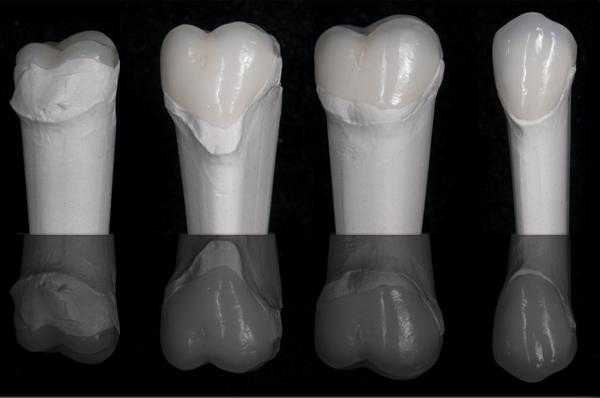

После этого в лаборатории были изготовлены vonlays (фото 10-14). Для этого авторы статьи обычно используют e.max в области моляров, ведь успехи подобного подхода уже хорошо задокументированы, но иногда можно использовать и полевошпатную керамику, особенно в случаях с достаточным количеством эмали, или когда премоляры лечат параллельно с установкой виниров на фронтальных зубах. Авторы по-прежнему предпочитают использовать протокол тотального протравливания с бондом 4-го поколения, хотя перспективы «универсальных» адгезивов и результаты, полученные в ходе их исследований, тоже не могут не радовать. На фото 15-29 продемонстрировано восстановление дуги верхней челюсти с использованием виниров во фронтальной области и керамических vonlays-конструкций на жевательной группе зубов.

Фото 10-13. В ходе работы были использованы модель Геллера и рефракторные штампики.

Фото 14. Вид vonlays (Vita Vm13).